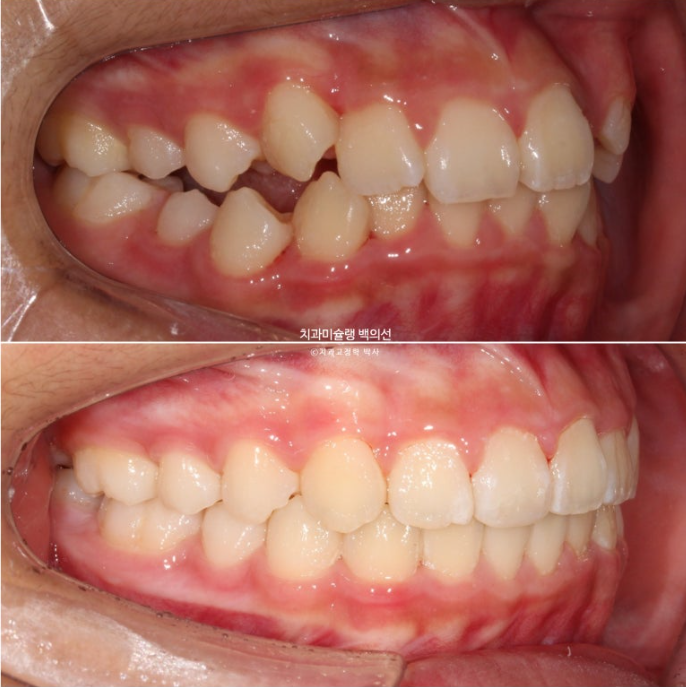

공간부족으로 인한 덧니가 심해 반대교합이 있습니다.

악궁확장을 통한 덧니배열을 목표로 인비절라인퍼스트 교정치료 권유드렸습니다.

어긋난 중심선이 맞아졌으며 기울어진 앞니 치축도 좋아졌습니다.

앞니가 깊게 물리는 과개교합도 좋아졌습니다.